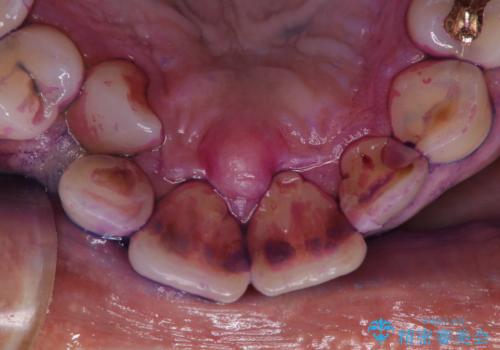

- 被せ物の治療が終了したためメンテナンスに入る前に全体的なチェック・クリーニングを行いました。

歯科衛生士による専門的なクリーニングPMTC(保険外治療)60分コースを行いました。

専門的な機械・材料を使用して徹底的に汚れを取り除きました。

染め出しをして、磨き残しの確認・ブラッシング指導も行いました。